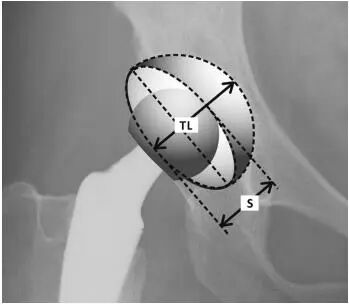

2.Widmer’s method:S是椭圆的短轴,TL是构件沿短轴投影横截面的总长度。这种方法对S/TL值在0.2和0.6之间显示出线性相关性(图2)。Version = arcsin (S/TL) = 48.05×(S/TL)–0.3 (if 0.2<S/TL<0.6)